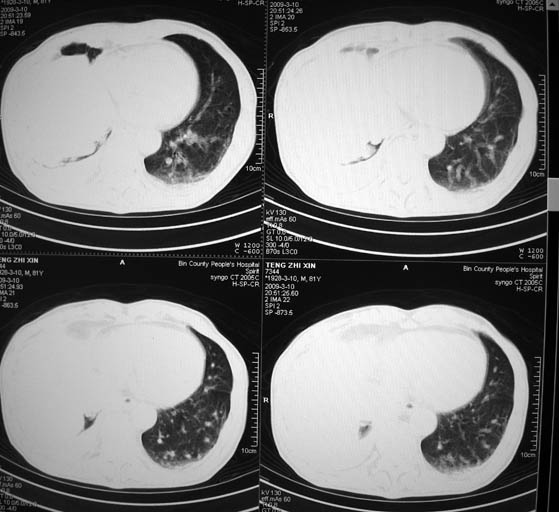

标题: CT18642:男,81岁,发热待查。

男,81岁,发热待查,右侧是占位还是膈疝?

右肺中央型肺癌并两侧胸水,左肺转移,腹水

1)考虑右肺下叶中央型肺癌并左肺转移。2)两肺上叶结核(陈旧性)。3)双侧胸腔积液。4)腹水。

右肺癌并双肺及胸膜转移。

右肺癌并双肺及胸膜转移

右中央型肺癌并双肺及胸膜转移